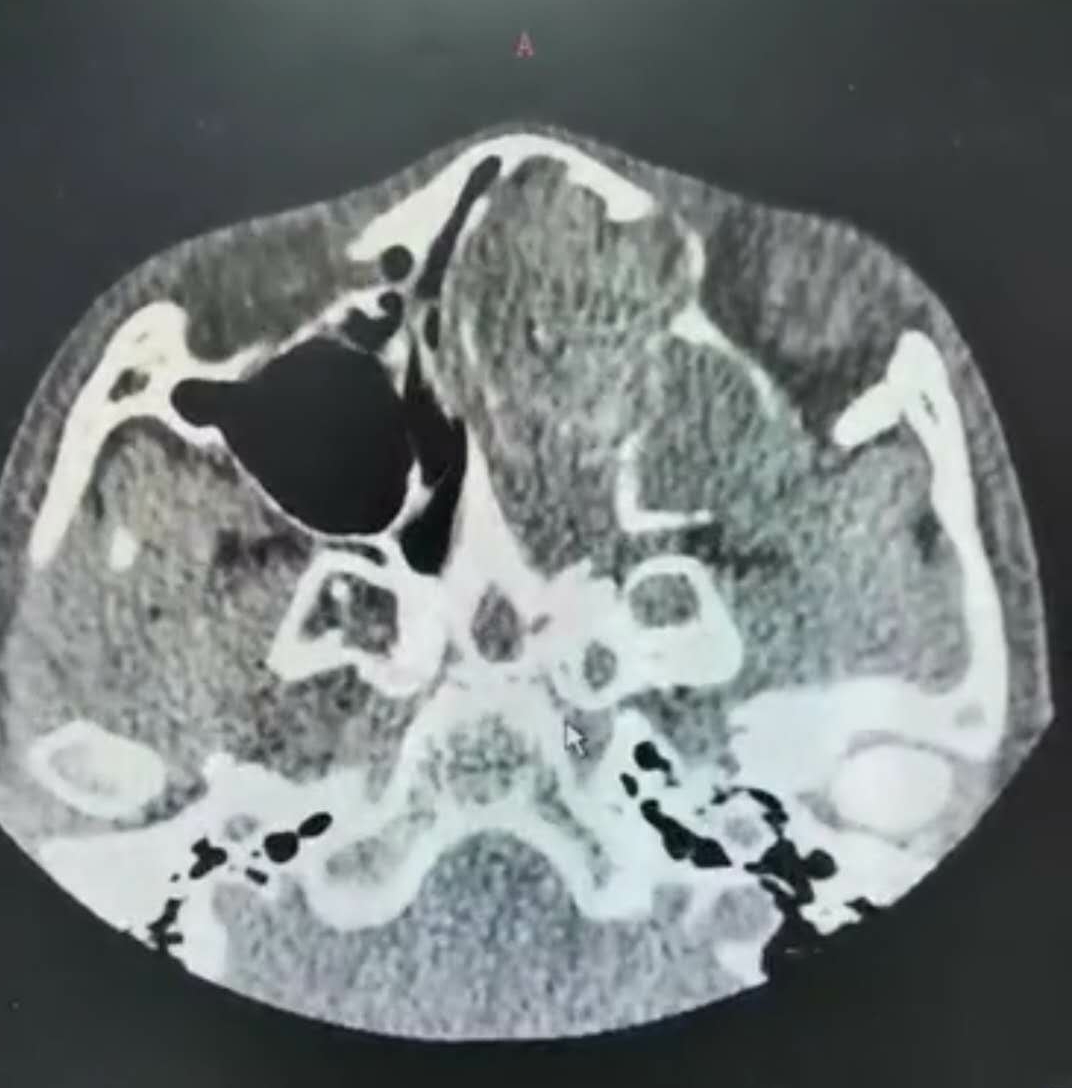

我举起CT片子一看,真把我吓了一跳!片子里左侧鼻腔、鼻窦里满是软组织肿物,正常结构都看不清了,鼻中隔也被压迫的严重右偏,而且肿物已将眼球向外推移!这么重的鼻息肉在儿童里太少见了!

“你看,和右眼相比,这左眼有点向外突起,左边的鼻梁也比右边高一些”,我用手分布捂住孩子的左眼和右眼,差别一下就显现出来了。